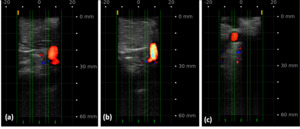

To generate the data sets needed for training of the SonoVision™ algorithm and to determine the device’s ease of use, a combination of benchtop research as well as animal and human studies was employed. First, the capability of the ultrasound system to identify nerves in a variety of different tissues was confirmed. This was accomplished through both an in-vivo rabbit study and a cadaveric study wherein accurate nerve detection by SonoVision™ ultrasound was confirmed by dissection. Once appropriate evidence of the system’s ability to identify nerves was observed, it was prudent to demonstrate that the algorithm driving the software and imaging system was not restricted to simple and controlled scenarios. To this end, an institutional review board approved study confirmed the ability of the SonoVision™ system to locate femoral or ulnar peripheral nerves at various tissue depths in 52 different patients. Following the success of this study, the training dataset was further improved through a subsequent in-vivo porcine study that introduced complex and dynamic tissue environments to assess imaging at multiple disc levels and validate bone targeting functions. At this juncture, testing of the imaging system in a simulated operating room workflow was identified as the next best step.

A simulated usability study applied the trained SonoVision™ ultrasound system with Beluga1TM probe to a surgical setting which was representative of what physicians would encounter in a real scenario. This study involved the use of 5 porcine subjects with all protocols previously approved by IACUC. The primary objective was to assess and validate the SonoVision™ system’s ability to locate nerves, vasculature, and bone and facilitate safe navigation around key soft-tissue structures to access the target disc space. Metal pins represented the “clear-path” to vertebral spaces identified using the system and the presence of nerves or vasculature were subsequently evaluated within the vicinity of each pin. Of the 24 pins placed in the 5 animals, all SonoVision™ imaging notes matched with the corresponding dissection notes representing a 100% accuracy for all tissue type identification (Figure 10).